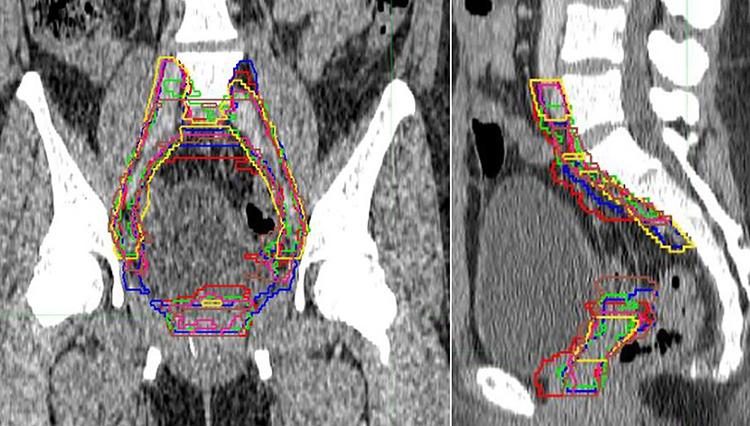

The postoperative hypofractionated intensity-modulated radiation therapy (POHIM-RT) trial is a phase II study to evaluate toxicity following hypofractionated intensity modulated radiation therapy (IMRT) for cervical cancer. This study describes the results of a benchmark procedure for RT quality assurance of the POHIM-RT trial. Six participating institutions were provided computed tomography for RT planning and an IMRT plan for a sample and were instructed to delineate volumes, create a treatment plan and quality assurance (QA) plan, and submit the results of all procedures. The inter-institutional agreements on RT volume and plan results were evaluated using the kappa value and dice similarity coefficients. The simultaneous truth and performance level estimation (STAPLE) method was employed to generate a consensus target volume. The treatment volumes, organs-at-risk volumes, and results of the RT plan and QA reported by the institutions were acceptable and adhered well to the protocol. In terms of clinical target volume (CTV) delineation, there were differences between the institutions, particularly in vaginal cuff and paracolpium subsites. Consensus CTV was generated from the collected CTVs with the STAPLE method. The participating institutions showed considerable agreement regarding volume, dose and QA results. To improve CTV agreement in CTV, we provided feedback with images of the consensus target volume and detailed written guidelines for specific subsites that were the most heterogeneous.

术后大分割调强放疗(POHIM-RT)试验是一项II期研究,旨在评估宫颈癌大分割调强放疗(IMRT)后的毒性。本研究描述了POHIM-RT试验放疗质量保证基准程序的结果。为六个参与机构提供了用于放疗计划的计算机断层扫描和一个样本的IMRT计划,并指示它们划定靶区体积、制定治疗计划和质量保证(QA)计划,并提交所有程序的结果。使用kappa值和骰子相似系数评估机构间关于放疗体积和计划结果的一致性。采用同时真相与性能水平估计(STAPLE)方法生成共识靶区体积。各机构报告的治疗体积、危及器官体积以及放疗计划和QA的结果是可接受的,并且很好地遵循了方案。在临床靶区体积(CTV)划定方面,各机构之间存在差异,特别是在阴道断端和阴道旁组织亚部位。通过STAPLE方法从收集到的CTV中生成共识CTV。参与机构在体积、剂量和QA结果方面表现出相当高的一致性。为了提高CTV划定中CTV的一致性,我们提供了共识靶区体积的图像反馈以及针对最不均匀的特定亚部位的详细书面指南。